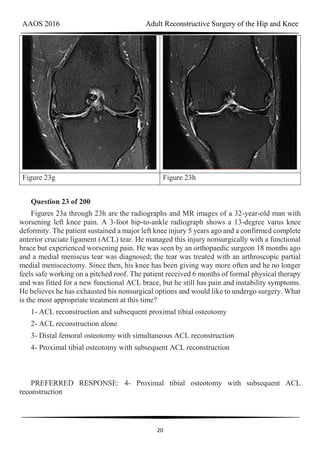

Figure 23a Figure 23b

Figure 23g Figure 23h

Question 23 of 200

Figures 23a through 23h are the radiographs and MR images of a 32-year-old man with

worsening left knee pain. A 3-foot hip-to-ankle radiograph shows a 13-degree varus knee

deformity. The patient sustained a major left knee injury 5 years ago and a confirmed complete

anterior cruciate ligament (ACL) tear. He managed this injury nonsurgically with a functional

brace but experienced worsening pain. He was seen by an orthopaedic surgeon 18 months ago

and a medial meniscus tear was diagnosed; the tear was treated with an arthroscopic partial

medial meniscectomy. Since then, his knee has been giving way more often and he no longer

feels safe working on a pitched roof. The patient received 6 months of formal physical therapy

and was fitted for a new functional ACL brace, but he still has pain and instability symptoms.

He believes he has exhausted his nonsurgical options and would like to undergo surgery. What

is the most appropriate treatment at this time?

1- ACL reconstruction and subsequent proximal tibial osteotomy

2- ACL reconstruction alone

3- Distal femoral osteotomy with simultaneous ACL reconstruction

4- Proximal tibial osteotomy with subsequent ACL reconstruction

PREFERRED RESPONSE: 4- Proximal tibial osteotomy with subsequent ACL

reconstruction

DISCUSSION

Proximal tibial osteotomy is the most appropriate intervention to correct varus

malalignment and to decrease stress on the ACL. In some cases, proximal tibial osteotomy

alone may address both pain and instability, but, if instability persists, particularly in the setting

in which instability can be dangerous, subsequent ACL reconstruction can further stabilize the

knee with less stress on the graft after correction of malalignment. Varus alignment places

increased stress on the native or reconstructed ACL. ACL reconstruction should only be

performed at the same time as or following proximal tibial osteotomy to correct alignment in

the setting of varus malalignment. It is not appropriate to perform ACL reconstruction prior to

proximal tibial osteotomy in this setting. Distal femoral osteotomy is not indicated to correct

varus malalignment. Varus alignment places increased stress on the native or reconstructed

ACL, and ACL reconstruction alone is not indicated for this patient.